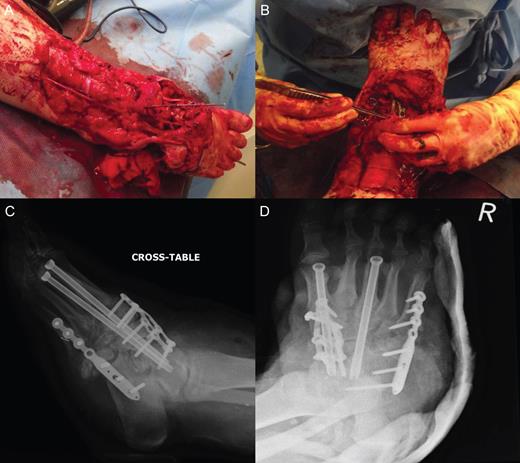

Wound debridement demonstrated pus at screw insertion sites with navicular and talar involvement. The patient had inadequate soft tissue coverage, bony osteomyelitis and necrotic bone. Primary limb shortening with a talectomy was conducted to reduce the soft tissue deficit and remove infected and necrotic bone, tibiocalcaneal arthrodesis for joint stability using external fixation, and dead space was treated with calcium sulphate mixed with vancomycin and systemic intravenous and oral antibiotics for osteomyelitis postoperatively (Figs 3 and 4). The wound was closed after the external fixator was applied. Wound swabs and bone samples revealed Enterococcus faecalis and E. raffinosus and diphtheroids. The patient was treated with intravenous teicoplanin and meropenem with oral stepdown to linezolid and ciprofloxacin.

External fixation used to facilitate tibiocalcaneal arthrodesis post talectomy. (A) Lateral view (B) Anterior posterior view.